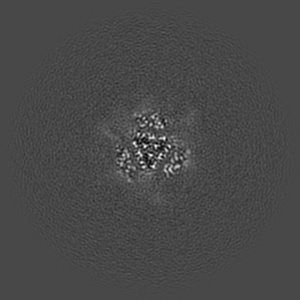

EMD-25986

Down-state locked rS2d SARS-CoV-2 spike ectodomain in the RBD-down conformation, State 2

Single-particle3.06 Å